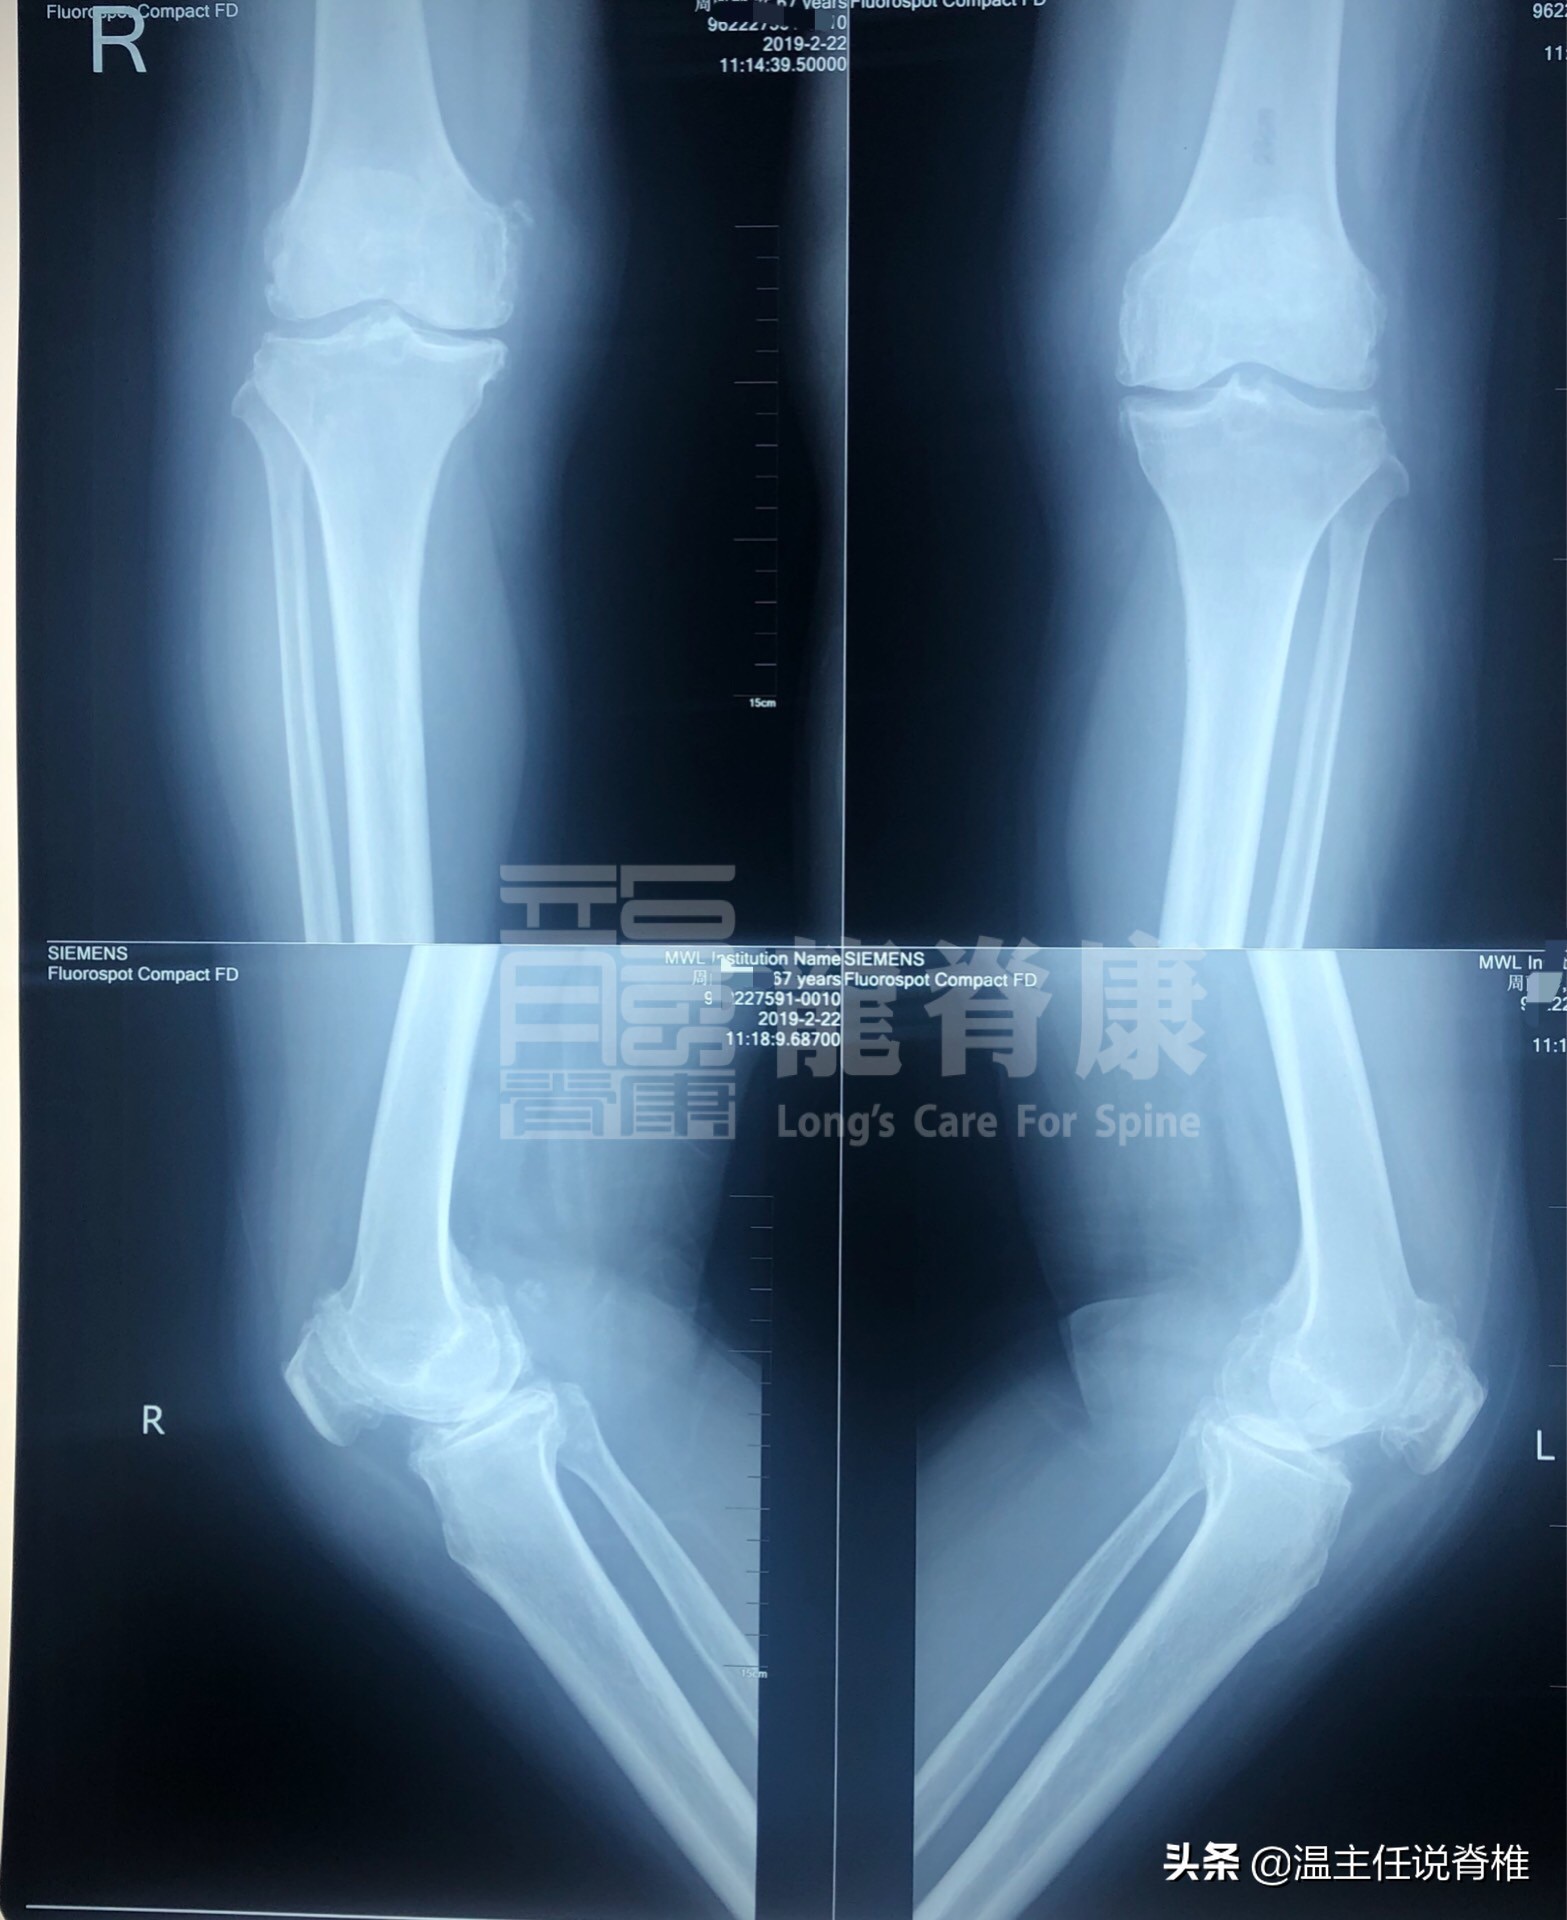

经仔细询问、触诊及X光辅助检查,综合周姨检查报告如下:

双膝关节内侧稍狭窄,双侧髌骨后缘增生硬化